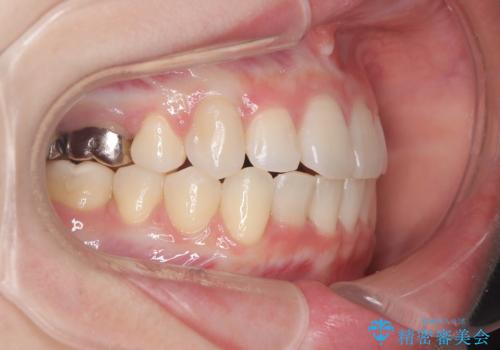

- 患者様は、下顎両側の第1大臼歯(6番)と右上6番の欠損を主訴に来院されました。

通常であればインプラントによる補綴が第一選択となる症例でしたが、患者様ご自身がインプラントを希望されなかったため、矯正治療によって欠損部の閉鎖を図る方針としました。

ワイヤー矯正を用いて、欠損部の閉鎖を目的とした後方からの歯の挺出・移動を行いました。

特に、親知らずを活用し、奥歯の噛み合わせを構築することに重点を置きました。

最終的には予定通りインプラントを使用せずに欠損部を閉鎖し、咬合も安定させることができました。